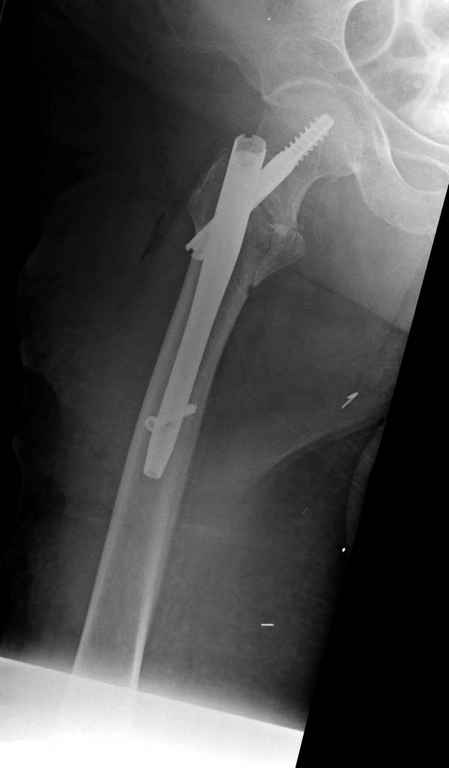

Re: Чрезвертельный перелом бедра

С приходом менее агрессивных блокируемых цефаломедуллярных гвоздей (Gamma 3 и другие) изменилась тактика лечения. Несмотря на то, что вся стабильность держится вокруг одного блокирующего винта, в большинстве случаев гвозди приводили к успеху.

Вашему вниманию представляется похожий случай, пациентке 70, осложнился в течение одного месяца после операции. Ревизия с заменой сустава, кабельная фиксация на трохантер. При установке в дистальном диафизе обнаружен тонкий кортикальный слой и сделана профилактика от возможного перелома аллографтом.